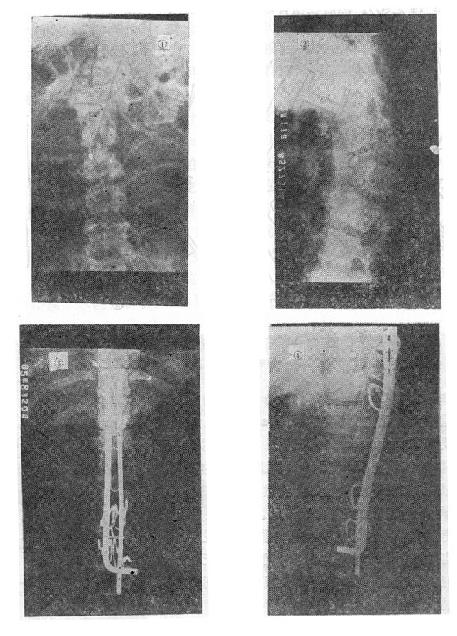

图73-15 椎体后部Chance骨折的治疗 (五)切片状骨折的治疗 因为这种骨折伴有整个韧带的完全撕裂,且常合并截瘫,用Harrington撑开棍治疗后方间隙反而会明显增宽。应选用强度较好的Luque或Dick装置为好,不仅能获得满意的复位(图73-16①~③),而且固定牢固,术后即可随意翻动病人,术后1-2即可让病人起床坐轮椅活动,有利于截瘫病人的康复与护理。

图73-16 切片骨折的治疗 (六)胸10以上的高位胸椎骨折截瘫 由于病人腰部的肌肉完全麻痹,会发生麻痹性侧弯和后凸畸形,用Harrington或Luque技术治疗,均不能解决腰椎固定到骨盆上的问题,所以都不能维持病人坐姿。由于腰骶部过度屈伸活动,很容易引起断棍、脱钩或钢丝的疲劳断裂(图73-17)。目前Galveston手术是解决这种骨折的最有效的方法。手术时作胸3~骶2正中切口,骨膜下剥离T3-4至S1-2、及髂后上嵴及髂骨外板,如Luque方法在T3-4至L5,每个椎板下穿过Luque钢丝。然后将事先弯好生理性胸后凸与腰前凸的两根金属棍,用Luque钢丝从胸3~4一直固定到髂骨坐骨切迹上方内外骨板之间。不仅牢固固定了骨折,而且能有效维持病人的坐姿(图73-18①②)。